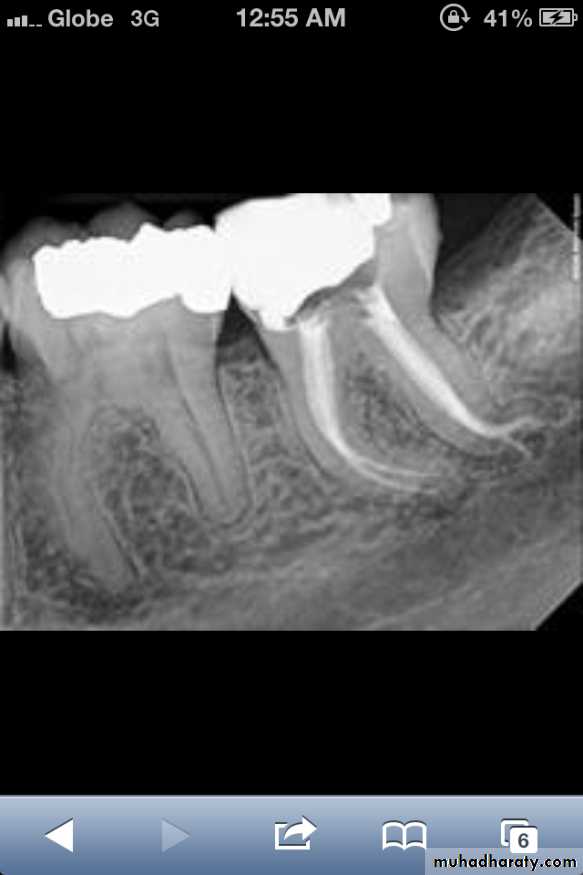

*Taurodont teeth have longitudinally enlarged pulp chambers.

*The crown is of normal shape and size, but the body is elongated and the roots are short.*The pulp chamber extends from a normal position in the crown throughout the length of the extended body, leading to an increased distance between the CEJ and the furcation.

Taurodontism

It may be associated with : Oral-facial-digital Syndrome.

Amelogenesis Imperfecta-Type IV,Down Syndrome.No treatment is required.